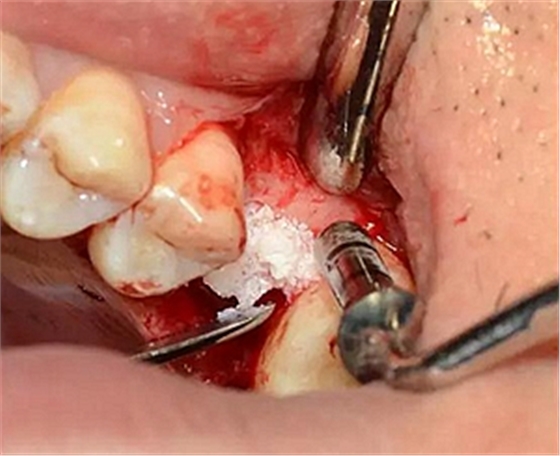

用配套工具進(jìn)行水壓式?jīng)_頂,提升竇膜。手感力反饋和回吸正常。在沖壓水量上要控制,緩慢反復(fù)多次抽吸,確保竇粘膜提升均勻。

逐次添加少量骨粉,加壓到位,反復(fù)進(jìn)行。骨粉總量約0.25g